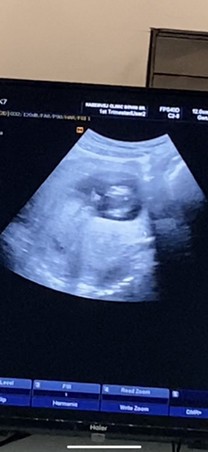

คุมหมอบอกว่าคล้ายผู้ชายงับ แม่ๆท่านไหนเคยอัลตราซาวด์แล้วเห็นแบบนี้ ผู้ชายจริงไหมงับ❤️❤️❤️❤️

บ้านนี้ เห็นแบบนี้ค่ะแม่ หมอว่าน่าจะผู้ชาย รอซาวยืนยันอีกที วันที่25 นี้จ้า